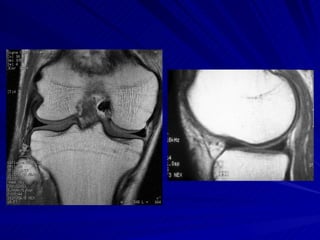

Joelho O estudo do joelho por RM é seguramente o método de imagem mais eficiente para demonstrar a anatomia e as eventuais alterações degenerativas e/ou decorrentes de traumas nesta articulação.

LIGAMENTOS CRUZADOS LCA – eminência intercondiliana da tíbia Porção medial do côndilo femoral lateral LCP – mais forte e mais curto Fossa intercondiliana posterior Porção lateral do côndilo femoral medial

Joelho O estudodo joelho por RM é seguramente o método de imagem mais eficiente para demonstrar a anatomia e as eventuais alterações degenerativas e/ou decorrentes de traumas nesta articulação.

LIGAMENTOS CRUZADOS LCA– eminência intercondiliana da tíbia Porção medial do côndilo femoral lateral LCP – mais forte e mais curto Fossa intercondiliana posterior Porção lateral do côndilo femoral medial